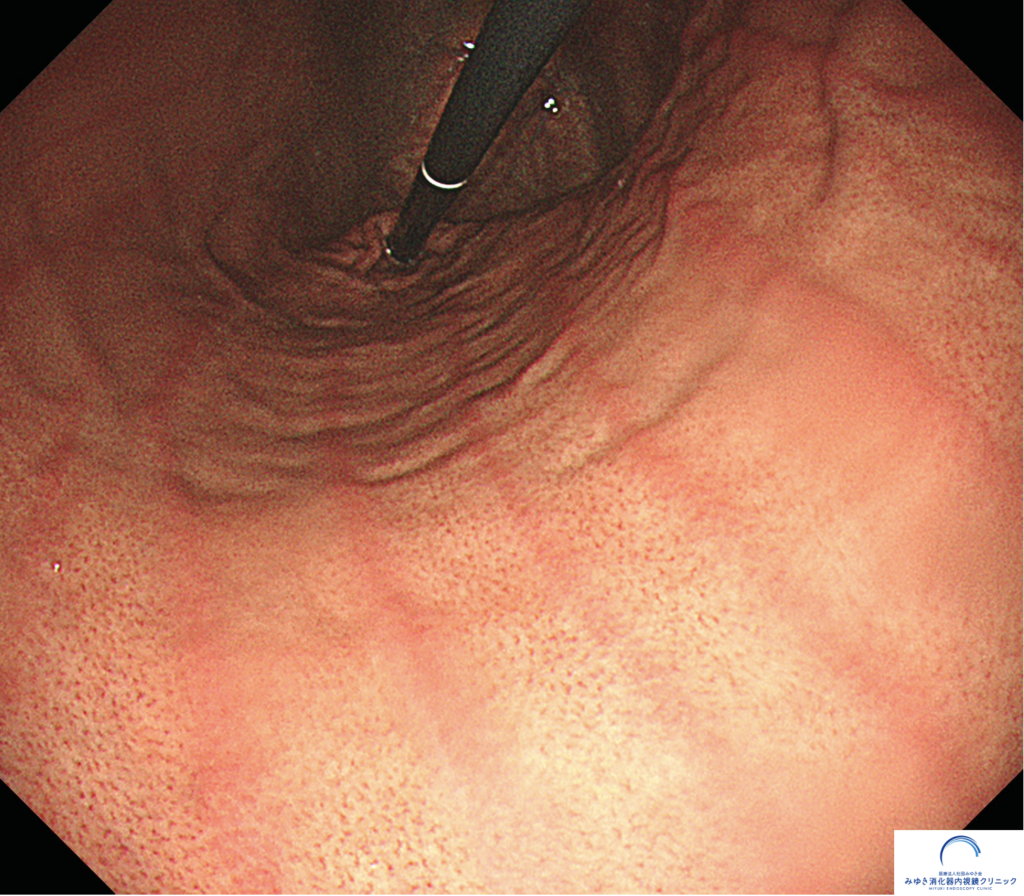

当院で行った胃カメラ検査では、正常な胃粘膜は全体的にきれいで、正常な胃粘膜と考えられる所見でした。胃体部にはRAC(ラック)が明瞭に確認でき、ピロリ菌感染を疑う所見は認められませんでした。

胃カメラで見える正常な胃の粘膜は、光沢があり、ツヤがあります。また胃のひだも細く真っ直ぐに伸びています。

② RAC(ラック)

胃体部から胃角部には多数のヒトデ様の発赤点が規則正しく並んでいるのが確認できます。これは「RAC(ラック)」と呼ばれるもので、その正体は胃の粘膜内の血管です。このRACの有無を判定することが非常に大事で、RACが確認できれは95%以上の確率でピロリ菌がいないと判定することができます。